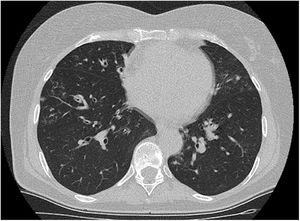

A los 2meses y medio se repitió la TC torácica, que mostró persistencia de las bronquiectasias, imágenes nodulares y adenopatías con desaparición de las discretas áreas en vidrio deslustrado (fig. 1). Las pruebas de función respiratoria, análisis de autoinmunidad y coagulación fueron normales.

Se ha descrito un predominio de esta infección en mujeres con una edad media de 60 años, similar a la edad de la paciente que presentamos. Habitualmente, su evolución es benigna; sin embargo, existe un caso publicado de neumonía necrosante con derrame pleural paraneumónico en un paciente inmunocompetente5. Radiológicamente, suele presentarse como bronquiectasias, nódulos o imágenes de árbol en brote y se ha descrito como agente causal de sobreinfección de bronquiectasias preexistentes6.